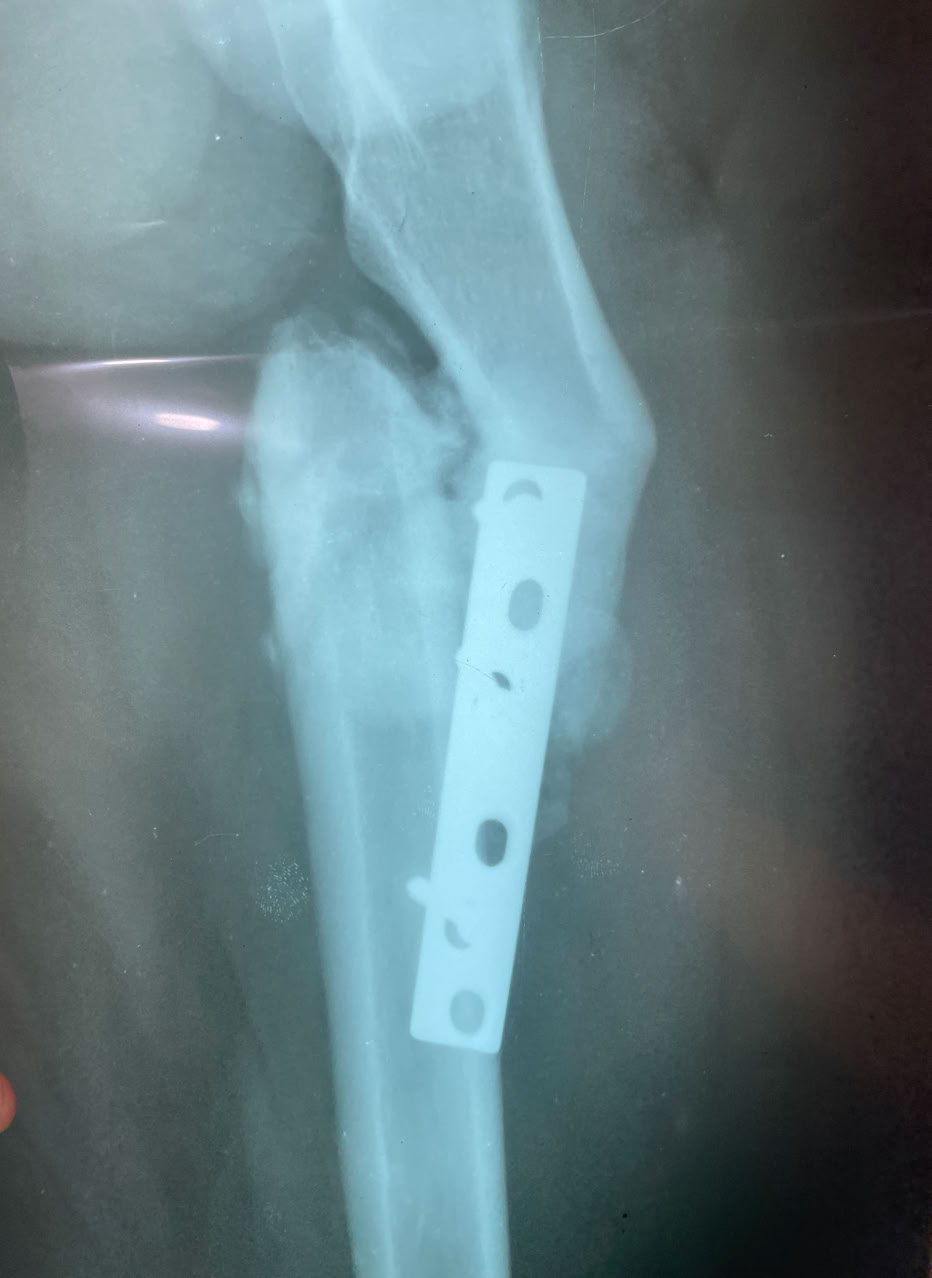

Como siempre, el trabajo no falta y hemos atendido diversas urgencias. Sirva como ejemplo el clásico “PANADIZO CAMERUNÉS” y las fracturas abiertas de tibia.

Aquí presentamos un par de estos casos, consecuencia la mayoría de las veces por tratar fracturas complejas con masajes y acudir a nosotros muchos meses después.

Hemos tenido como siempre casos de alta complejidad que hemos tenido que resolver en quirófano,. Desde que disponemos de los dos quirófanos las sesiones son mas relajadas y se operan mas enfermos.